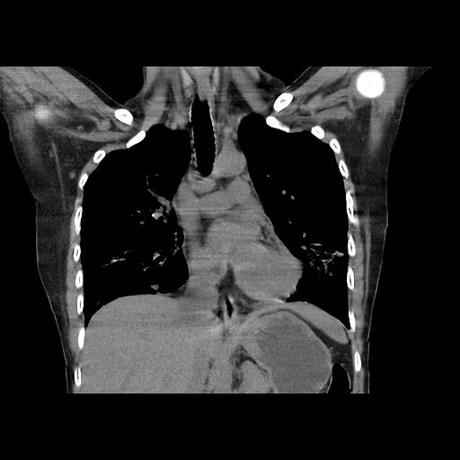

Se realiza volumen de tórax en fase simple, desde los opérculos torácicos hasta los hemidiafragmas, observándose:

El parénquima pulmonar con areas parcheadas difusas en vidrio despulido combinadas con otras areas hipodensas de baja atenuación debidas a atrapamiento aéreo y engrosamiento intersticial y zonas de fibrosis de predominio en lóbulos medios e inferiores de ambos pulmones.

La pleura se encuentra conservada, sin engrosamientos.

- LOS HALLAZGOS PUEDEN ESTAR EN RELACIÓN A NEUMOPATIA INTERSTICIAL PROBABLE ETIOLOGIA HIPERSENSITIVA VS AUTOINMUNE/BACTERIANA/FUNGICA.